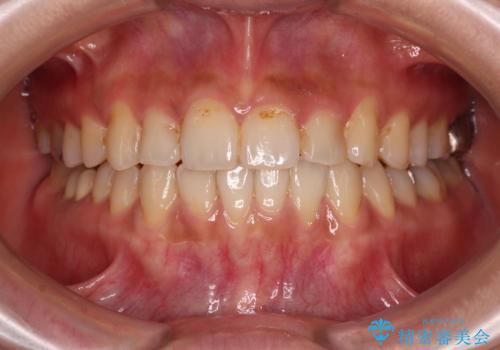

- くちばしのような前歯の突出感を気にして来院された患者様です。

上下左右第一小臼歯4本を抜歯して、積極的に口元を引っ込めるよう、ワイヤー装置にて矯正治療を行うこととしました。